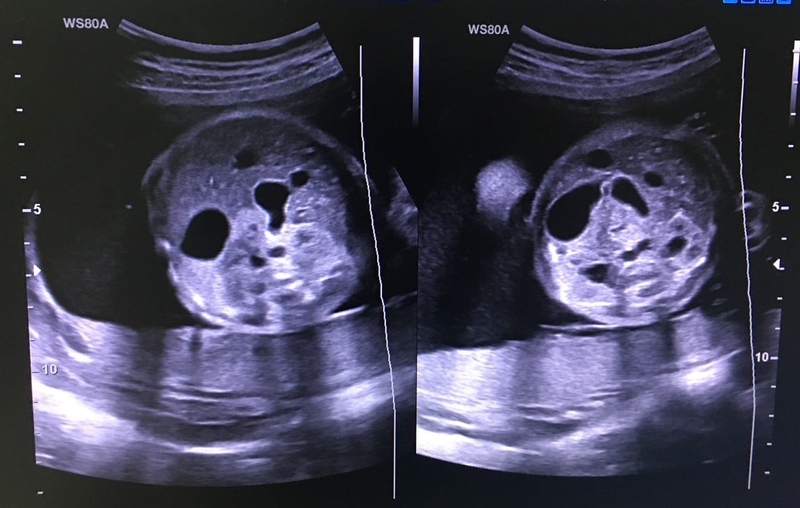

Triệu chứng của tắc tá tràng được thể hiện ở 2 giai đoạn là trước sinh và sau sinh. Dấu hiệu siêu âm trước sinh giúp chẩn đoán bệnh tắc tá tràng bẩm sinh:

• Dấu hiệu bóng đôi: Dấu hiệu này cho thấy sự tích tụ của chất lỏng do tắc nghẽn.

• Chụp X-quang bụng đứng: Khi nghi ngờ tắc tá tràng, chụp X-quang bụng thẳng đứng là phương tiện hình ảnh đầu tiên được sử dụng sau khi sinh. Dấu hiệu đặc trưng của tắc nghẽn tá tràng là hình bóng đôi của một dạ dày chứa đầy không khí và phần đầu tiên của tá tràng.